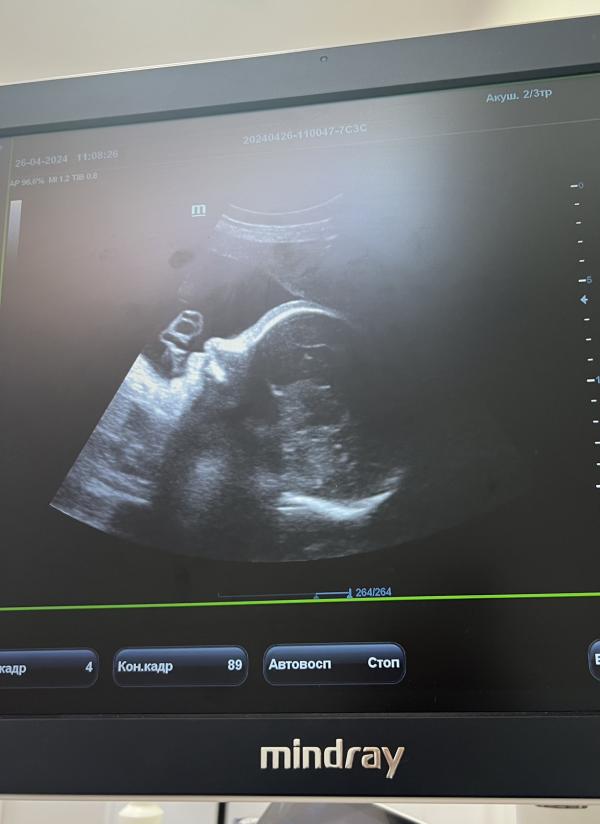

И вот уже 24.04.24 - мой первый скрининг в жк. Мне не нравится, как меня осмотрели и что мне даже экран не показали, а я так ждала нашей встречи с малышочком.

Записываюсь на повторный скрининг в частную клинику. И пусть я была спокойна и уверена в том, что с ним все хорошо, лишний раз убедиться в этом никому не помешало.

По узи все отлично, малышок растет, во время приема икал🥹